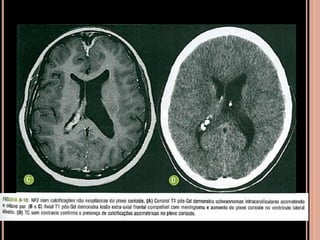

Achados de imagem NF2

 Schwannomas vestibulares (realce homogêneo

pelo contraste, seria hipo em T1)

 Meningeomas (realce intenso pelo contraste)

 Calcificação assimétrica de plexo corióide

 Schwannomas volumosos se estendendo para a

cisterna pontocerebelar com intensa impregnação

pelo Gd; na sequência em T2 tem hipersinal

heterogêneo;

 Múltiplos nódulos, em T1 pós contraste importante

realce compatíveis com schwannomas;

 Iso ou hipoatenuante em relação ao parênquima e realce pelo meio

de contraste, no ângulo pontocerebelar;

 Schwannomas vestibulares

 Schwannoma de nervo trigêmio